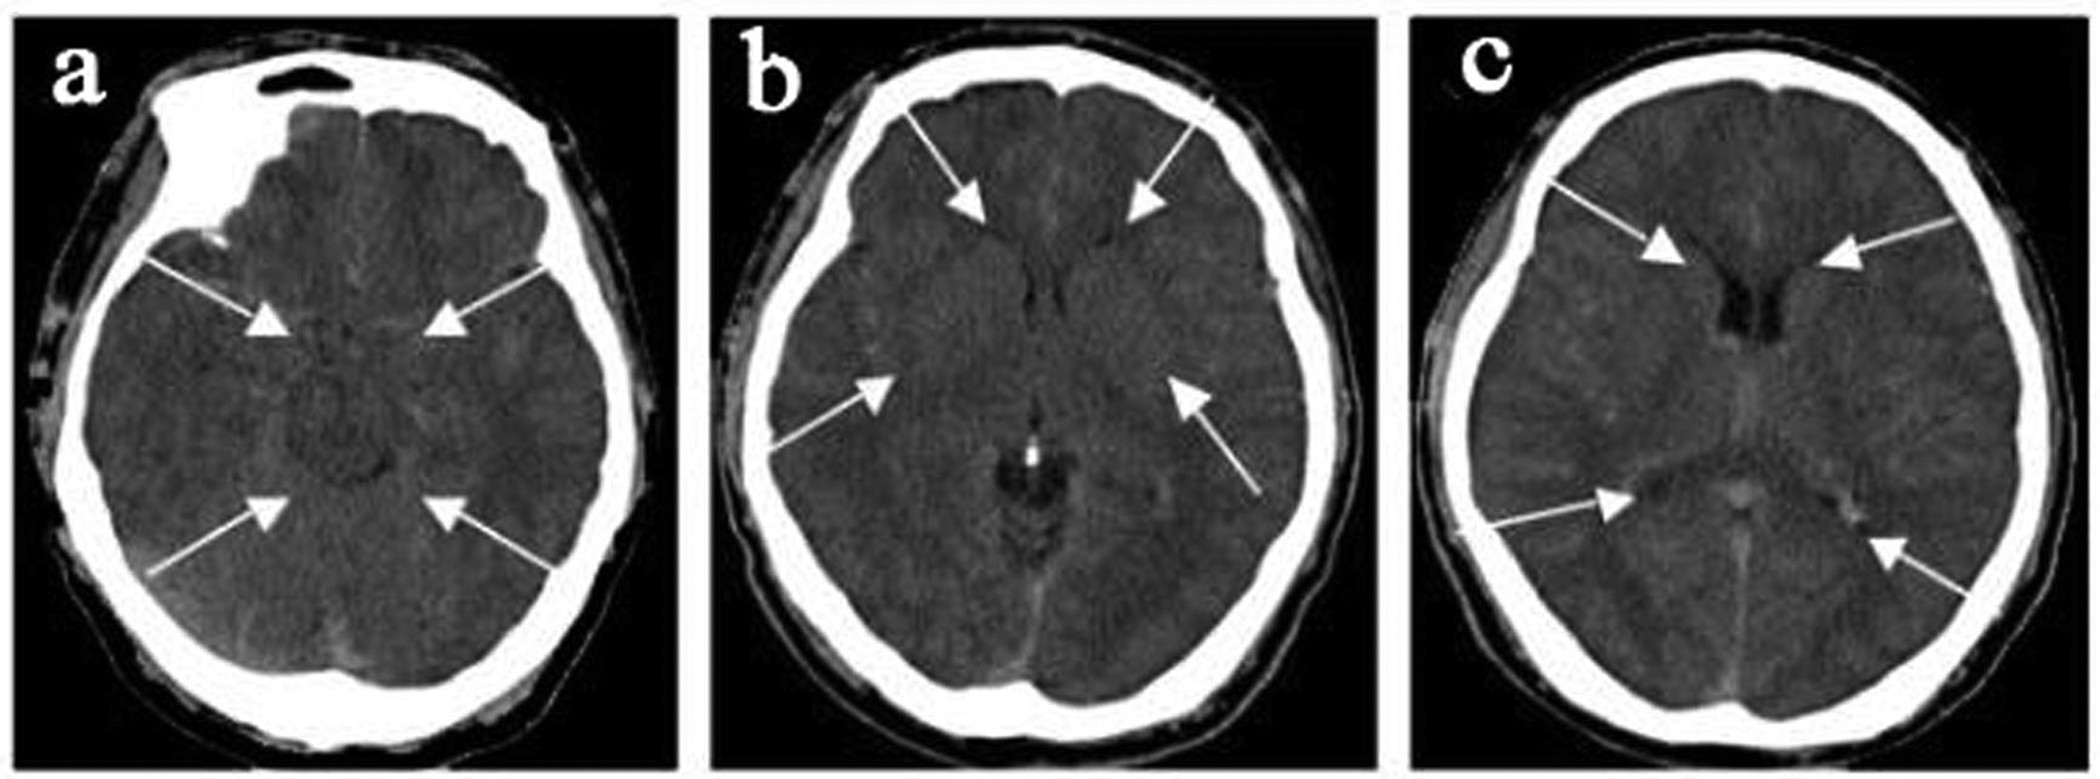

Figure 1: CMS patient, a 46-year-old male, hemoglobin 24.1 g/dl.

CT shows diffuse cerebral edema with small ventricles (c), effaced sulci (b,c), and compromised cisterns (a,b).